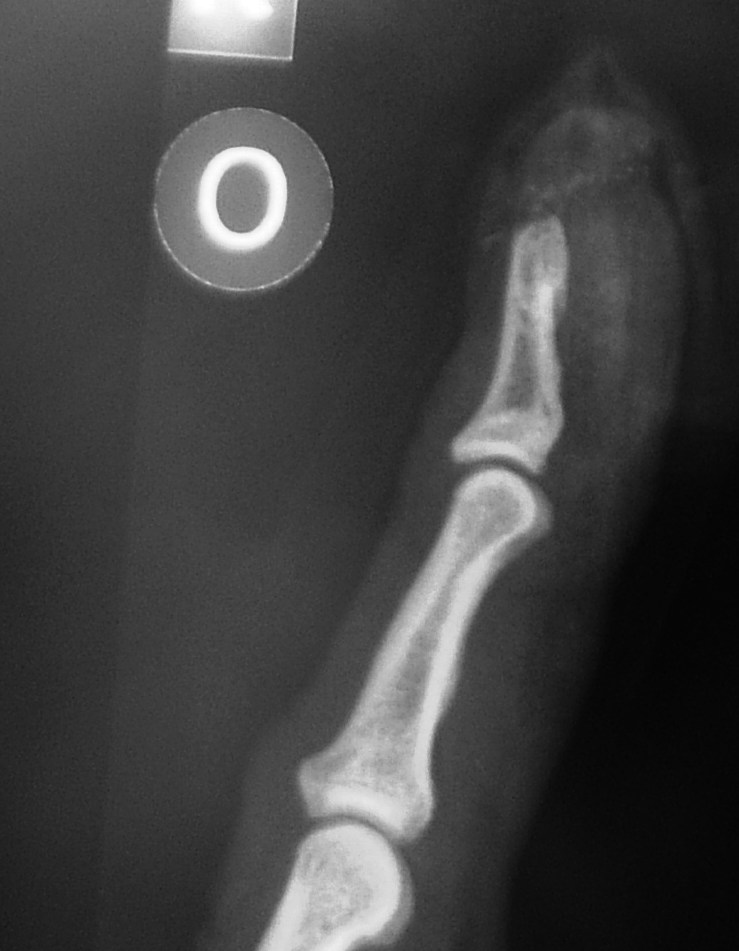

I noticed that the little wire wheel that knocks the swarf off the big bandsaw blade wasn't going round, tried to give it a flick and got sucked in to the machinery.

Saw the plastic surgeon today, he spent 20 minutes removing the swarf, popped what was left of the nail off and then stitched it back together right as dodgers. Looks a lot better now the gore has gone.

I may yet lose the tip but the worry is I nicked the end off the bone which may become infected. The most amazing thing though is, so far, the only painful bit has been the Lignocaine injections :heehee:

Attachment 2321

I did duck out for a fag at Eastbourne General and found a camera in my car. A bit out of focus being taken left handed without my specs, but it is available.

I see from the xray that you swallowed your wedding ring to stop the paramedics pinching it lol

lol, yes took us a long time to work that out... its the zipper on my cycling top... despite being plastic it sems to be opaque to xrays